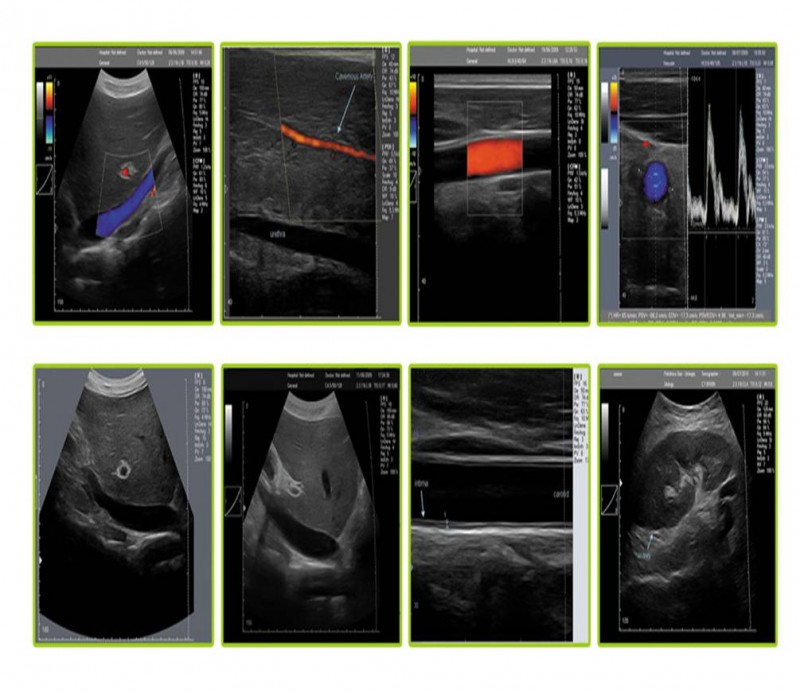

?超聲介入引導(dǎo)系統(tǒng)是針對(duì)經(jīng)外周靜脈穿刺中心靜脈置管(PICC)、靜脈中心置(CVC)和各種類型的神經(jīng)阻滯等手術(shù)可視化需求而專門設(shè)計(jì)的一款??朴貌食?。配有獨(dú)特的穿刺引導(dǎo)系統(tǒng),在幫助醫(yī)護(hù)人員獲得高質(zhì)量超聲圖像的同時(shí)通過(guò)智能化操作引導(dǎo)功能,進(jìn)行快捷、方便的診斷操作。

超聲介入引導(dǎo)下的深靜脈穿刺和各種類型的神經(jīng)阻滯利用超聲原理實(shí)現(xiàn)可視化技術(shù),已經(jīng)逐步成為麻醉學(xué)科發(fā)展的重要方向,另外在淺靜脈置管、PICC置管、CVC置管、胸腔穿刺、術(shù)中影像檢測(cè)、在腫瘤科、神經(jīng)外科、腎內(nèi)科ICU、急診急救等方面也廣泛應(yīng)用。